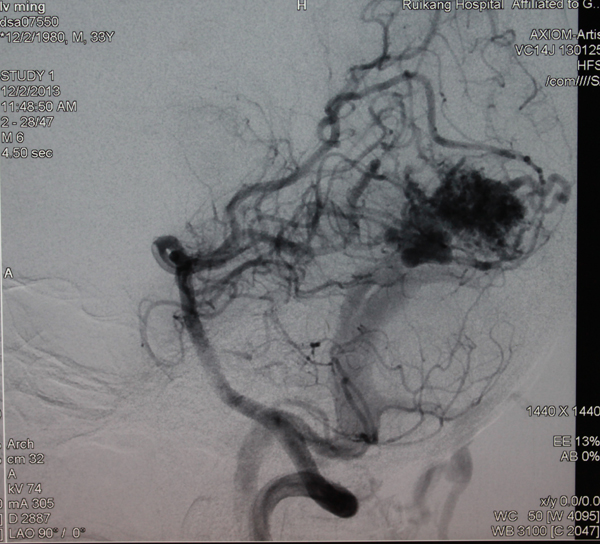

由于没有明显外伤,神经外科主治医师李亚平对病情进行分析后判断,李明很有可能是动静脉畸形导致的脑出血,从而引起头痛头晕,失去知觉。在明确病因后,李医生通过开颅手术将动静脉畸形进行切除,挽救了李明的生命。

李医生解释,李明患上的病准确的说是右枕叶动静脉畸形并出血。动静脉畸形,是动静脉之间缺乏正常毛细血管联通,导致动静脉直接联通形成畸形血管团块,是一种先天的发育异常。在青年人多见,并且男性稍多于女性,64%在40岁以前发病。据文献报告,高发年龄为15到20岁,年轻人发病的危险高于老年人。动静脉畸形的后果,轻者出现失语、肢体偏瘫、意识障碍,癫痫,重者造成植物状态,乃至危及生命。

由于是先天性疾病,动静脉畸形在出血发病前很难察觉,但是可通过脑血管造影来确诊和指导治疗。医生提醒有头痛,头晕,肢体抽搐,血管杂音症状的年轻人切勿大意,应尽快到医院进一步明确病因。

手术前